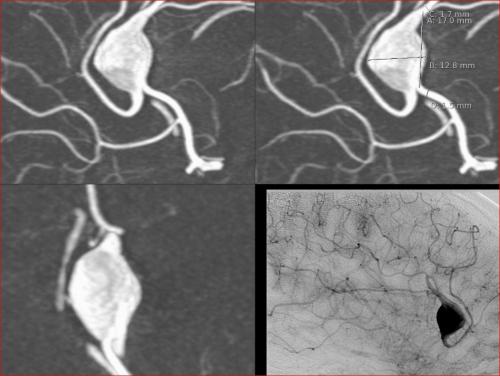

Aneurysma re. 7 mm Darstellung in einer DSA (digitalen Subtraktionsangiographie) links nur ein 2 mm „Baby-Aneurysma“ Im MRT war zuvor das linke Aneurysma aufgefallen, die Auflösung einer DSA ist technisch im MRT nicht erzielbar, beide A. liegen in der ACM Bifurkation jeweils, das re. Aneurysma wurde erfolgreich operiert, das linke Aneurysma wird kontrolliert.